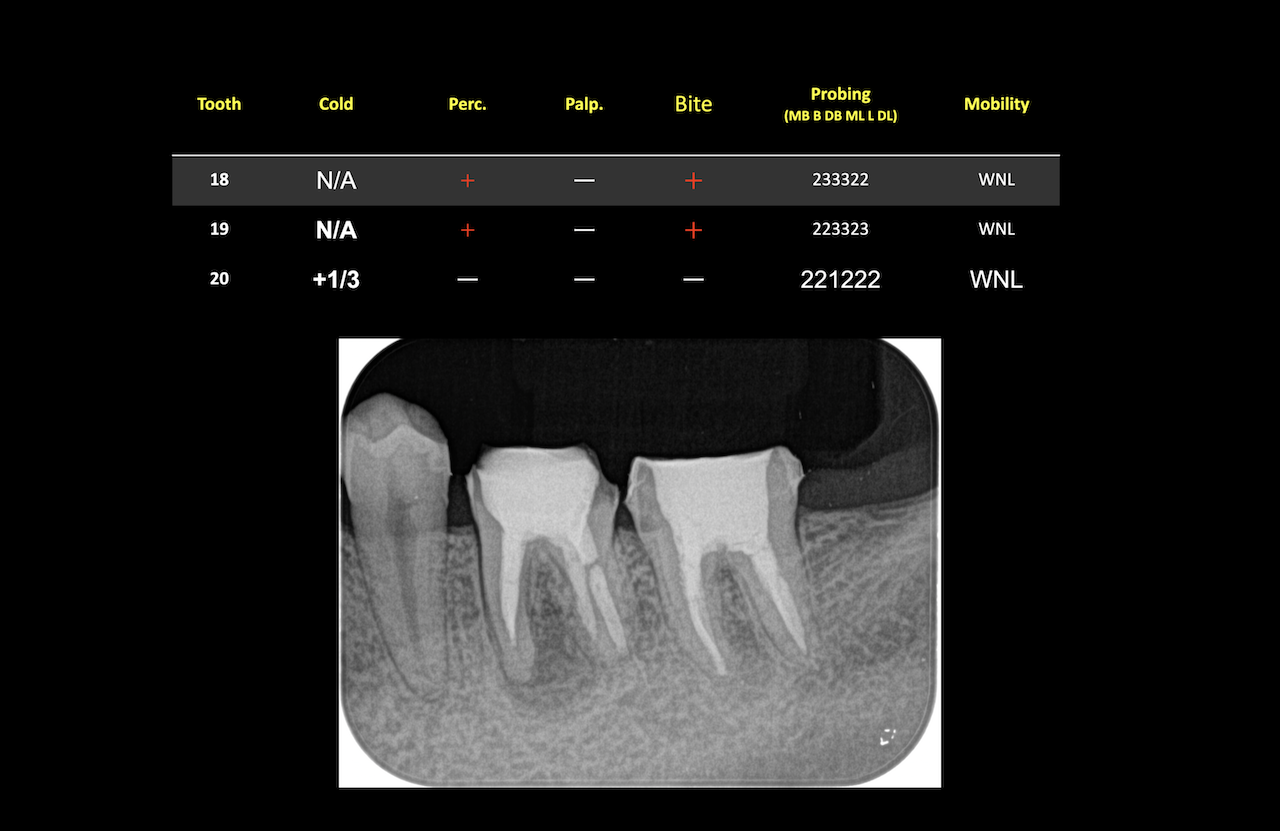

次に除冠せずにApicoectomyしていいのか?と言う話である。

研究では2年しか予後がないが私は7年も経過している症例がある。

ここが文献と臨床の違いだろう。